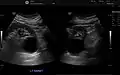

Simple renal cyst.jpg

Simple renal cyst